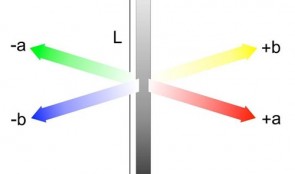

Analytical Methods: Assessment Of Esthetics And Color

based on the book chapter by Goran Benic and Irena Sailer Summary The visual appearance obtained after tissue reconstruction is an increasingly important aspect of orodental treatment, and hence of research. The esthetic aim is to achieve visual harmony between original and constructed elements. With a focus on metric assessment, the chapter offers guidance on the assessment of soft tissue levels and color matching, describing the scope and uses of ranking systems like the Copenhagen Index, Papilla Index and Implant Crown Esthetic Index, and the Pink/Pink and White Esthetic Scores. It describes how the common systems relate to different types of tissue and their optical, dimensional and surface characteristics, such as mucosal depth. While color match can be assessed using the naked eye, the growing demand for calibration and standardization makes electronic color analyzers more suitable, such as spectrophotometers, that use spectral analysis and CIE-Lab color coordinates and can be calibrated. Discussions cover all clinical parameters of interest and the factors that influence color match with the reconstruction material, such as mucosal thickness. The authors point out the need to make comparisons against healthy natural sites in the same patient, to standardize methods, minimize observer variations and ensure blind assessment. They also discuss how and when to establish baseline values to chart changes, and suggest suitable statistical analyses, with a view to publishing results the can be compared with relevant studies. Open full-text PDF (1.1 MB) -